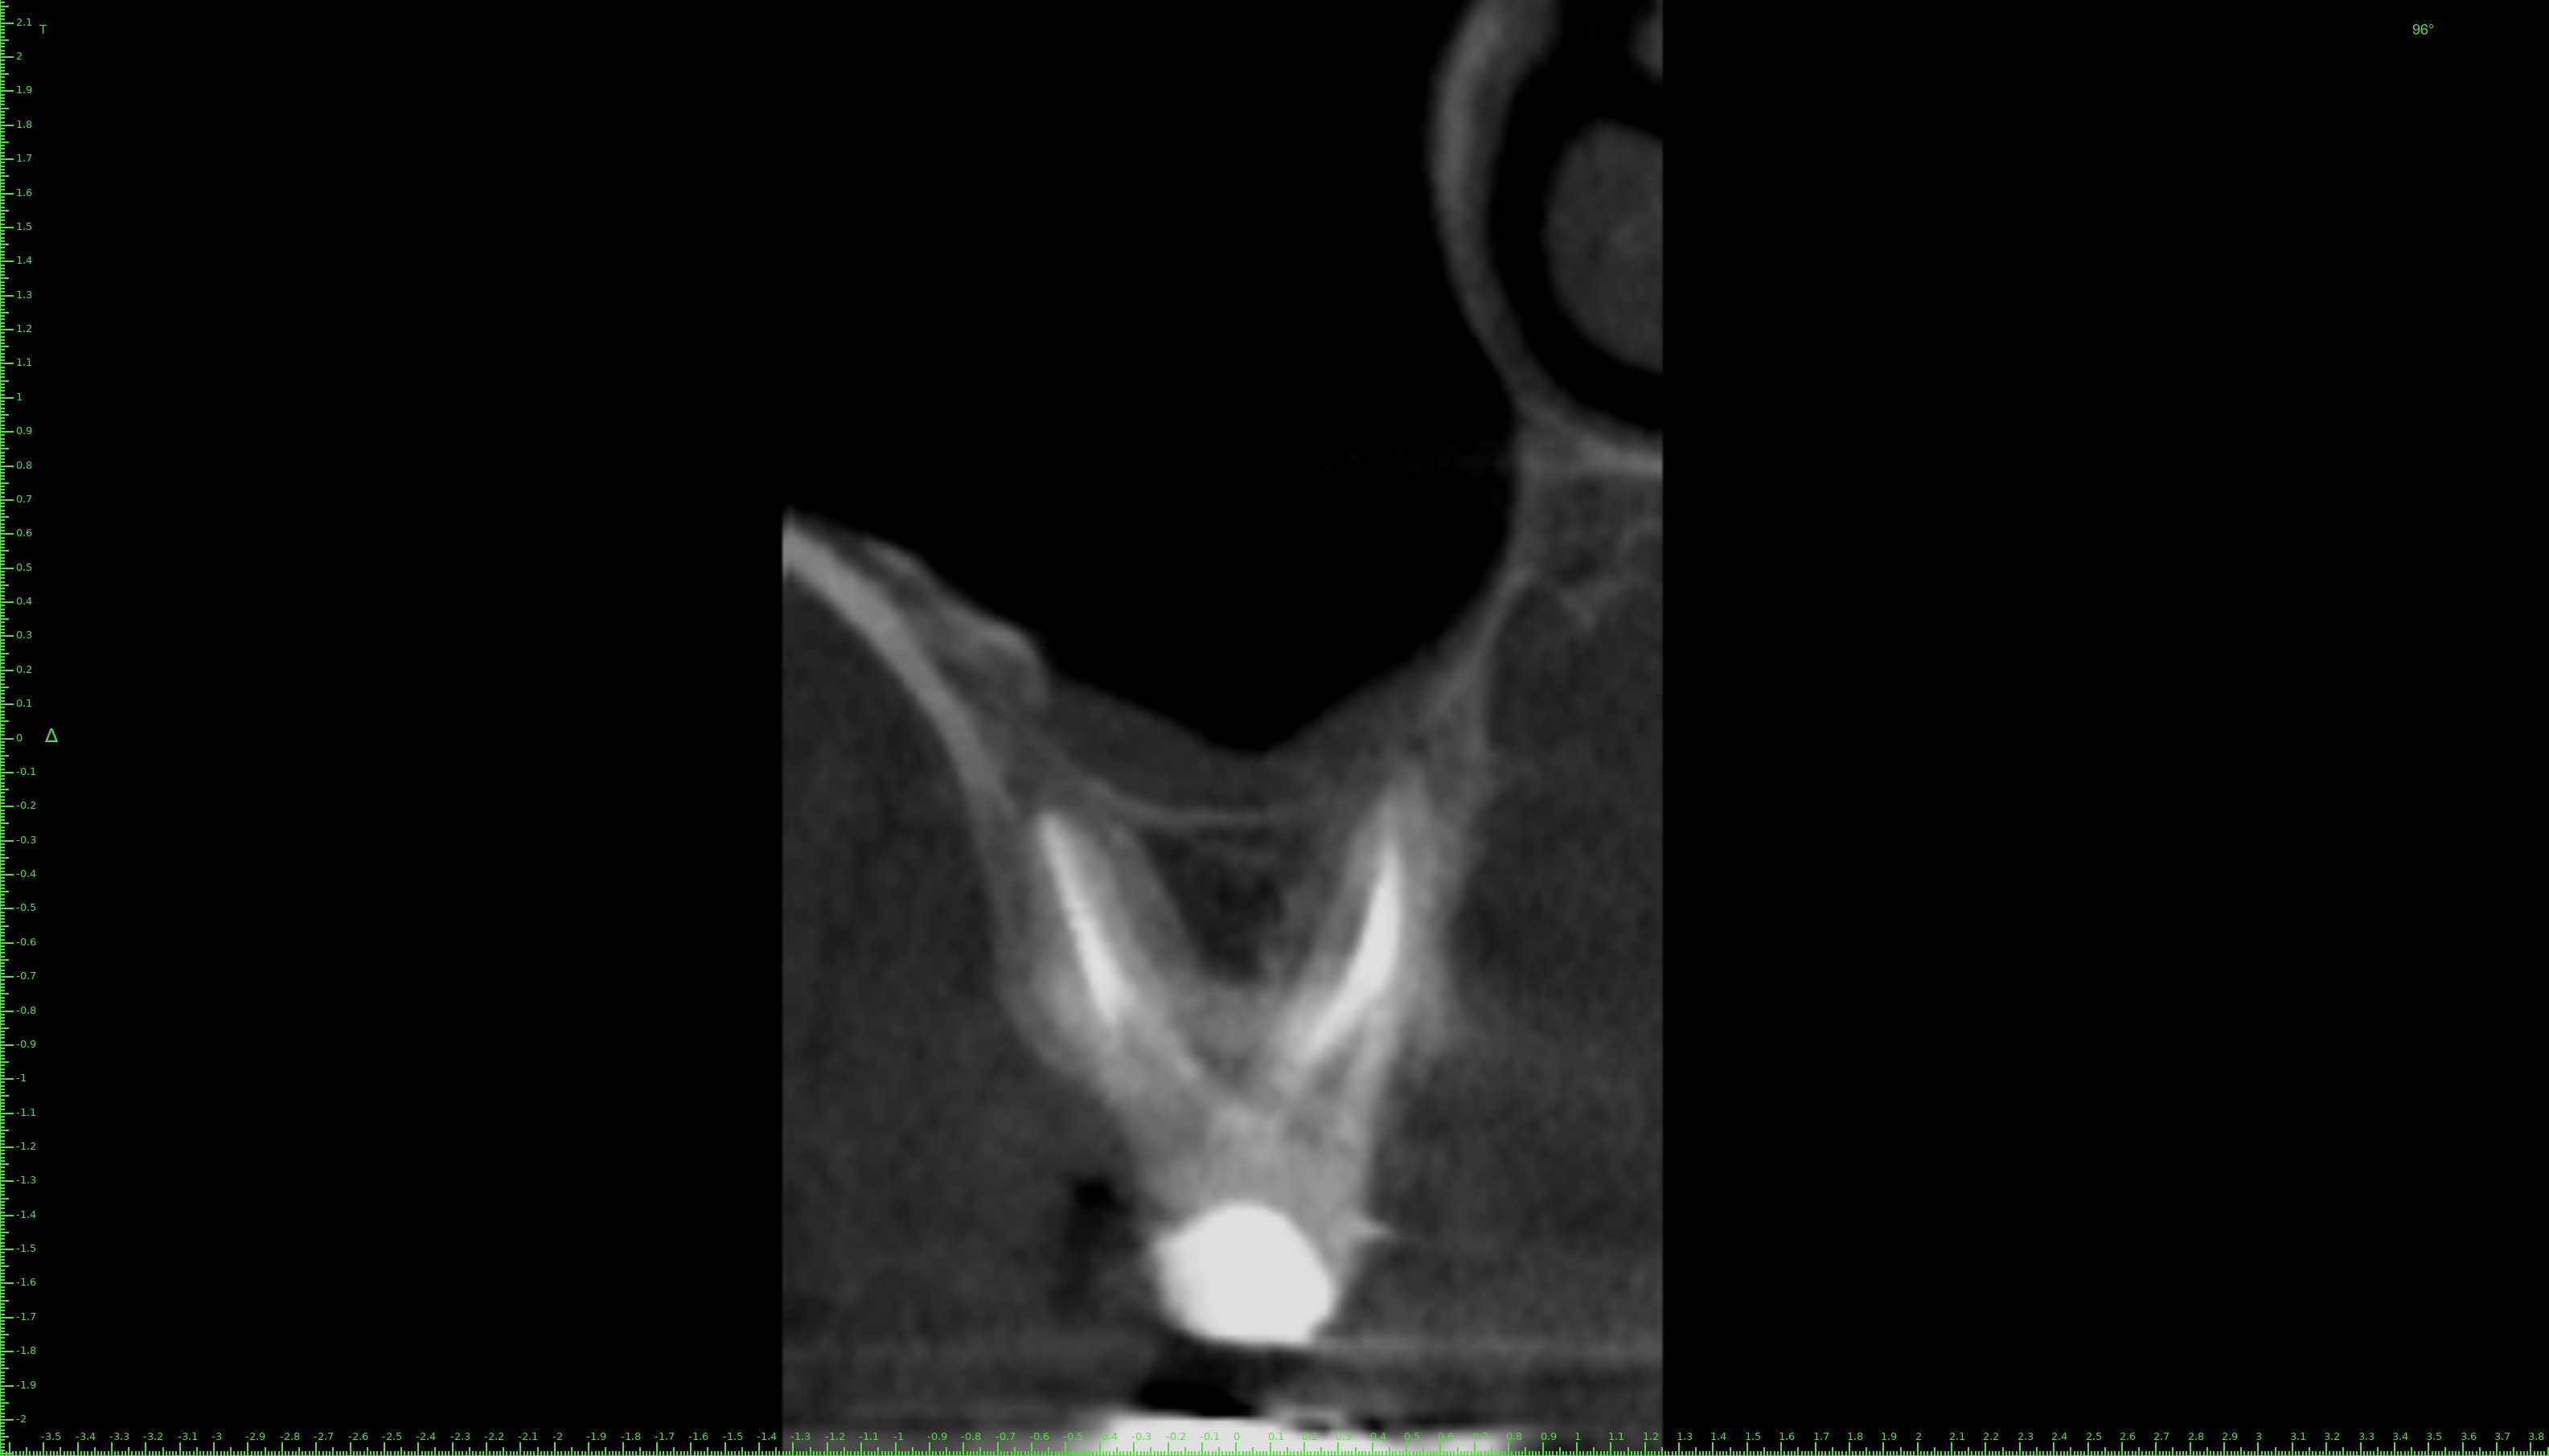

J'ai fait un conebeam de la 26.

L'obturation des racines est correcte, il y a juste une petite image apicale au niveau de la racine palatine avec un léger dépassement de pâte.

Pas de coupes horizontales ?

Le MV2 non obturé ici peut parfois, selon sa configuration, causer des douleurs variées.

Je peux me tromper, les coupes ne sont pas idéales pour conclure ☝️

Pour répondre à Dentarue: je viens de faire des coupes horizontale et centrées sur la racine vestibulaire en tournant autour d'un potentiel MV2. La gutta et le ciment font un joli artefact radio donc ce n'est pas concluant.

On le voit très bien sur ta 3d.

Aucune gloire, on ne voit que ça.

Chercher une deuxième entrée en vestibulaire quand on voit sur cette coupe et sur la coupe horizontale que c’est le palatin qui n’est pas obturé, … les mots me manquent.

Il cherche en vestibulaire de MV mais c’est en palatin de MV qu’il fallait chercher, cela me semblait aller sans dire ☝️

Tout est sur la 3d.

Le MV2 n’est pas très proche de la furcation mais plutôt plus mésial que le MV1. Il est très visible à la radio et ne doit pas être bien compliqué à traiter, mais pour ça il faut s’en donner les moyens et ça commence par la digue.

Tu nous dis qu’il n’y a pas de MV2 et tu nous montres des coupes où il saute aux yeux puis tu vois la patiente entre deux pour désobturer MV1 sans digue… et laisser MV2 non traité…